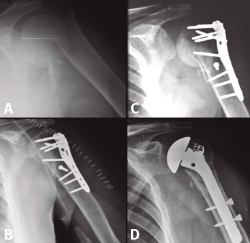

En el grupo que estamos analizando de pacientes en edad laboral con fractura compleja de húmero proximal su aplicación es limitada. Solamente quedaría indicado probablemente en pacientes mujeres mayores de 60 años con fracturas de 3 o 4 partes no muy desplazadas, con mala calidad ósea, un trabajo sin grandes requerimientos físicos y una vida extralaboral no muy activa (Figura 2). En estos pacientes la inmovilización con un cabestrillo de 4-6 semanas y la posterior rehabilitación funcional constituyen el tratamiento habitual.

Figura 2. Evolución radiológica del tratamiento conservador de una fractura de húmero proximal derecho. A: radiología simple anteroposterior; B: reconstrucción de la tomografía computarizada de la fractura de 4 partes desplazada; C y D: evolución radiológica del tratamiento conservador.